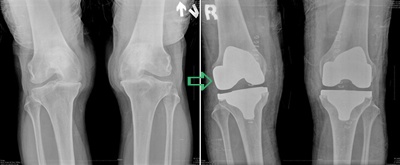

인공관절 수술은 심한 퇴행성관절염 치료에서 대표적으로 사용되는 것으로, 닳아 없어진 무릎 연골 대신 인체에 해가 없는 새로운 연골을 넣어 무릎관절의 통증을 없애주고 운동범위를 확보 하는 수술법이다. 하지만 인공관절은 말 그대로 인공장기이기 때문에 자기 관절과 100% 같지 않다. 통증을 줄이고, 운동범위를 확보해 주지만 자기관절이 아니기 때문에 마지막 수단으로 활용 되고 있다. 그렇다면 어떤 사람에게 인공관절이 필요한 것일까.

퇴행성 관절염의 진행과정을 보면 크게 초기, 중기, 말기 3가지로 나누어 볼 수 있다. 단계에 따라 증상도 다르고, 치료법도 다르다. 퇴행성 관절염 초기의 경우 무릎 주변 근육을 강화하는 운동을 실시해 주고, 때에 따라 통증이 심하면 주사치료를 한다. 초기에서 중기로 이동하면 관절 통증이 더욱 심해지는데 이때에는 주사치료와 같이 관절 내시경을 이용해 관절면을 다듬거나 손상된 연골을 재생해 주는 치료를 실시하게 된다. 하지만 뼈와 뼈 사이가 완전히 달라붙은 말기의 경우엔 수술밖에는 치료 방법이 없어 인공관절 삽입 수술을 받아야 한다.